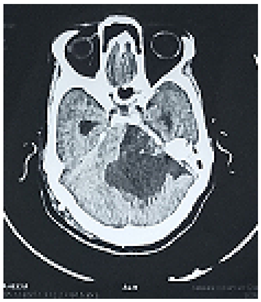

#Case 1:

This is 18years Sudanese young female, university student, an otherwise healthy before, presented to neurosurgery emergency unit with history of rabidly progressing headache for 6 months duration, few weeks before her appearance she exhibit visual blurring that end in decrease visual acuity in both eyes, she has inability to walk steady.

Neurological examination, revealed conscious patient, with just perception to light and there was increase tone and exaggerated reflexes on both lower limbs.

Operation: Before the decision of surgery, we talked to the patient and her family clearly about the surgery complications and post operative outcome. Through left tempro- parito-occipital craniotomy, the tumor was macroscopically totally resects. It was sub cortical, well circumscribed ill define capsule, extended deeply to the underlining temporal horn of the lateral ventricle .Dural graft was taken from the tempralis fascia and was closed in water tide.

Patient was fully recovered from anesthesia and was taken to the ICU on nasal oxygen mask.

Histopathology

Brain tubeclomata ( extra pulmonary tuberculosis)

Patient was put on anti-tuberculosis according to the international protocol, and discharged free of headache, can see objects.